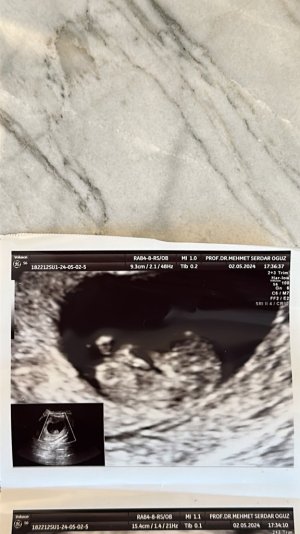

Nub teorisine göre bebeğimin cinsiyeti?

Kimler kimler yazdı?Nuba göre mi dediniz acabakız gibi

Bana da yorum yapar misinizkız gibi

kız gibi

Erkek gibicinsiyet tahmininde bulunurmusunuz kızlar11haftalık

Kız gibiNub teorisine göre bebeğimin cinsiyeti nedir acaba bilen anlayan var mı?

Bana da yorum yapabilir misinizKız gibi

Bence biraz daha büyümesi lazım. Yorum yapmak zor ama erkek gibimsi. Ama belli olmaz birkaç hafta daha büyüsün benceBana da yorum yapabilir misiniz

Bana kız gibi geldiTekrar yorum yapar mısınız cinsiyet icin

Bence erkekMerhabalar bende atsam tahminde bulunabilr misiniz doktorumuz hala cinsiyet Eki Görüntüle 3430849 hakkında yorum yapmıyor 21 haftaya girdik .13 haftalıkken kıza benziyor demişti 16 da erkeğe benziyor ama kordonda olabilir demişti